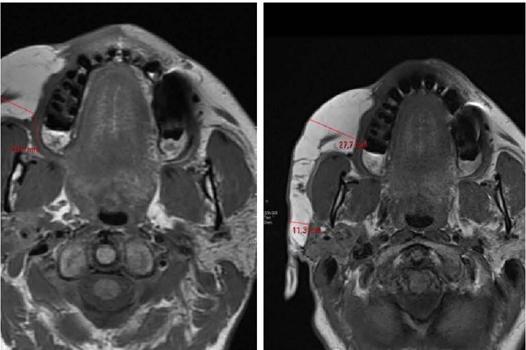

Paciente feminina, 59 anos, sem comorbidades, apresentou história de hemiatrofia facial à direita em região de terço médio e inferior da face, com atrofia de pele e subcutâneo estável aos 27 anos, porém sem causa definida e ausência de trauma ou doença local diagnosticada. Além disso, nenhuma alteração óssea ou neurológica estavam presentes e não havia nenhuma alteração no exame sistêmico e cutâneo. A paciente foi tratada com enxerto de gordura abdominal em hemiface direita por cirurgião plástico. Após um ano de cirurgia se queixa de aumento de volume na área tratada, com assimetria facial. Sendo assim, realizamos exame de Ressonância Magnética da face que evidenciou o acúmulo de tecido adiposo em hemiface direita na região geniana, estendendo-se às regiões mandibular e palpebral inferior, além de finos septos de permeio sem evidência de formação expansiva no interior da imagem. Os tecidos da hemiface esquerda mantinham configurações habituais (Figura 1). Dessa forma, optamos por tratar a hipercorreção cirúrgica com infiltração de ativos com ação lipolítica e antioxidante a fim de reduzir a gordura facial em hemiface direita. O produto utilizado foi a solução Toskani Silhouette Cocktail®, composta de agentes lipolíticos (cafeína e a 1-carnitina) e de substâncias antioxidantes (extratos de centelha asiática, alcachofra, ananás e chá verde), com aprovação na Agência Nacional de Vigilância Sanitária para uso tópico (número de registro 25351.147646/2023-03), porém utilizado, neste trabalho, por via de aplicação subcutânea de maneira off label por tratar-se de uso experimental. Foram realizadas nove sessões de aplicação do Toskani Silhoutte Cocktail® com intervalo de quinze dias entre as sessões. Nas primeiras quatro sessões aplicamos 3,2 ml da solução distribuídos em pontos de 0,lml a cada 1 cm, com agulha 0,30 X 13mm (30G) aplicada a uma profundidade de 4 a 6 mm em um ângulo de 45°, visando entregar as substâncias em plano subcutâneo. Após a quarta sessão realizamos 2 ampolas de ácido hialurônico em pontos de sustentação facial, seguindo a técnica Delta V Lifting*.6 Em seguida foram realizadas mais 5 sessões de aplicação do Toskani Silhouette Cocktail ®, aplicando-se 2,5ml da solução em cada sessão distribuídos em pontos de 0,lml a cada 1 cm. O resultado foi redução da hipercorreção cirúrgica, melhora evidente do volume de gordura da hemiface direita e aspecto menos granuloso da gordura à palpação (Figura 2). Realizamos novo exame de Ressonância Magnética da face que evidenciou redução do acúmulo de tecido adiposo em hemiface direita em comparação ao exame anterior e distribuição mais simétrica do mesmo (Figura 3). Além disso, observamos maior simetria facial e satisfação da paciente com o resultado. Acompanhamos a paciente durante 12 meses após o procedimento com manutenção do resultado e ausência de efeitos adversos. Além disso, é importante ressaltar que obtivemos o termo de consentimento da paciente para realização do tratamento proposto e que não houve qualquer tipo de cobrança da paciente nesse tratamento. Por se tratar de tratamento experimental, o trabalho enviado ao comitê de ética e pesquisa para aprovação da sua realização.